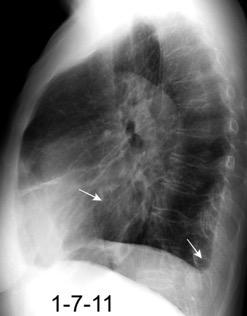

Tromboembolismo pulmonar Diafragma elevado 20%

Atelectasia crónica de LLI en paciente con enfermedad neuromuscular.